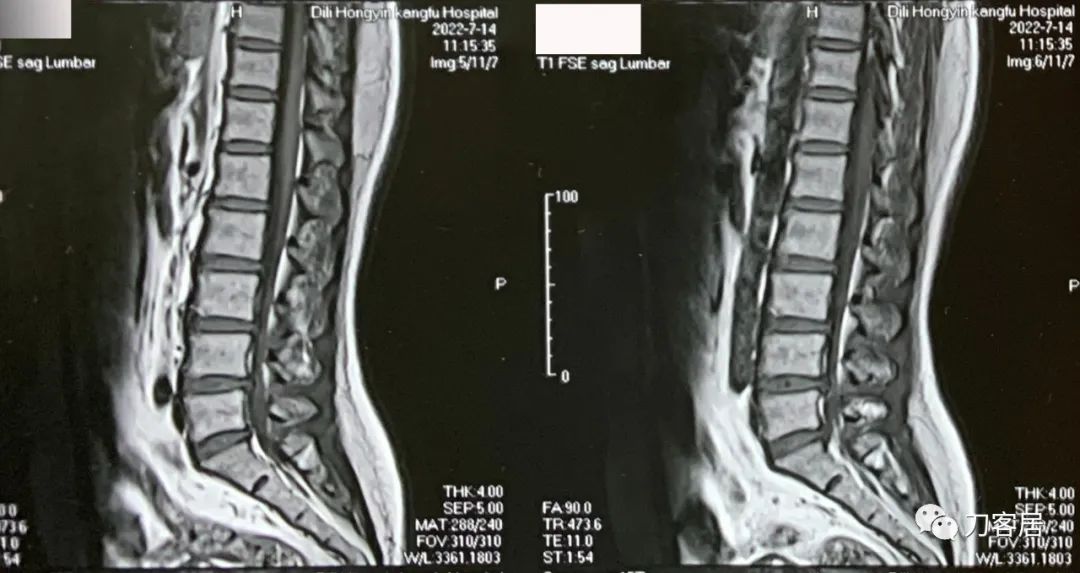

图1. 20220714外院腰椎MRI1,提示腰3-5椎间盘突出,椎管狭窄。

不能坐,晨起严重,姿势变化时明显,站卧无影响,坐姿后左臀部并左小腿抽痛麻,行走无影响。腰椎MRI提示腰3-5椎间盘突出,腰4-5,腰5骶1为重,腰5骶1左侧突出明显,并腰椎管狭窄。腰椎及骨盆X线片未见异常。骨密度提示骨量正常,且有所增高。昨日(8月4日)可连续行走1.6km。